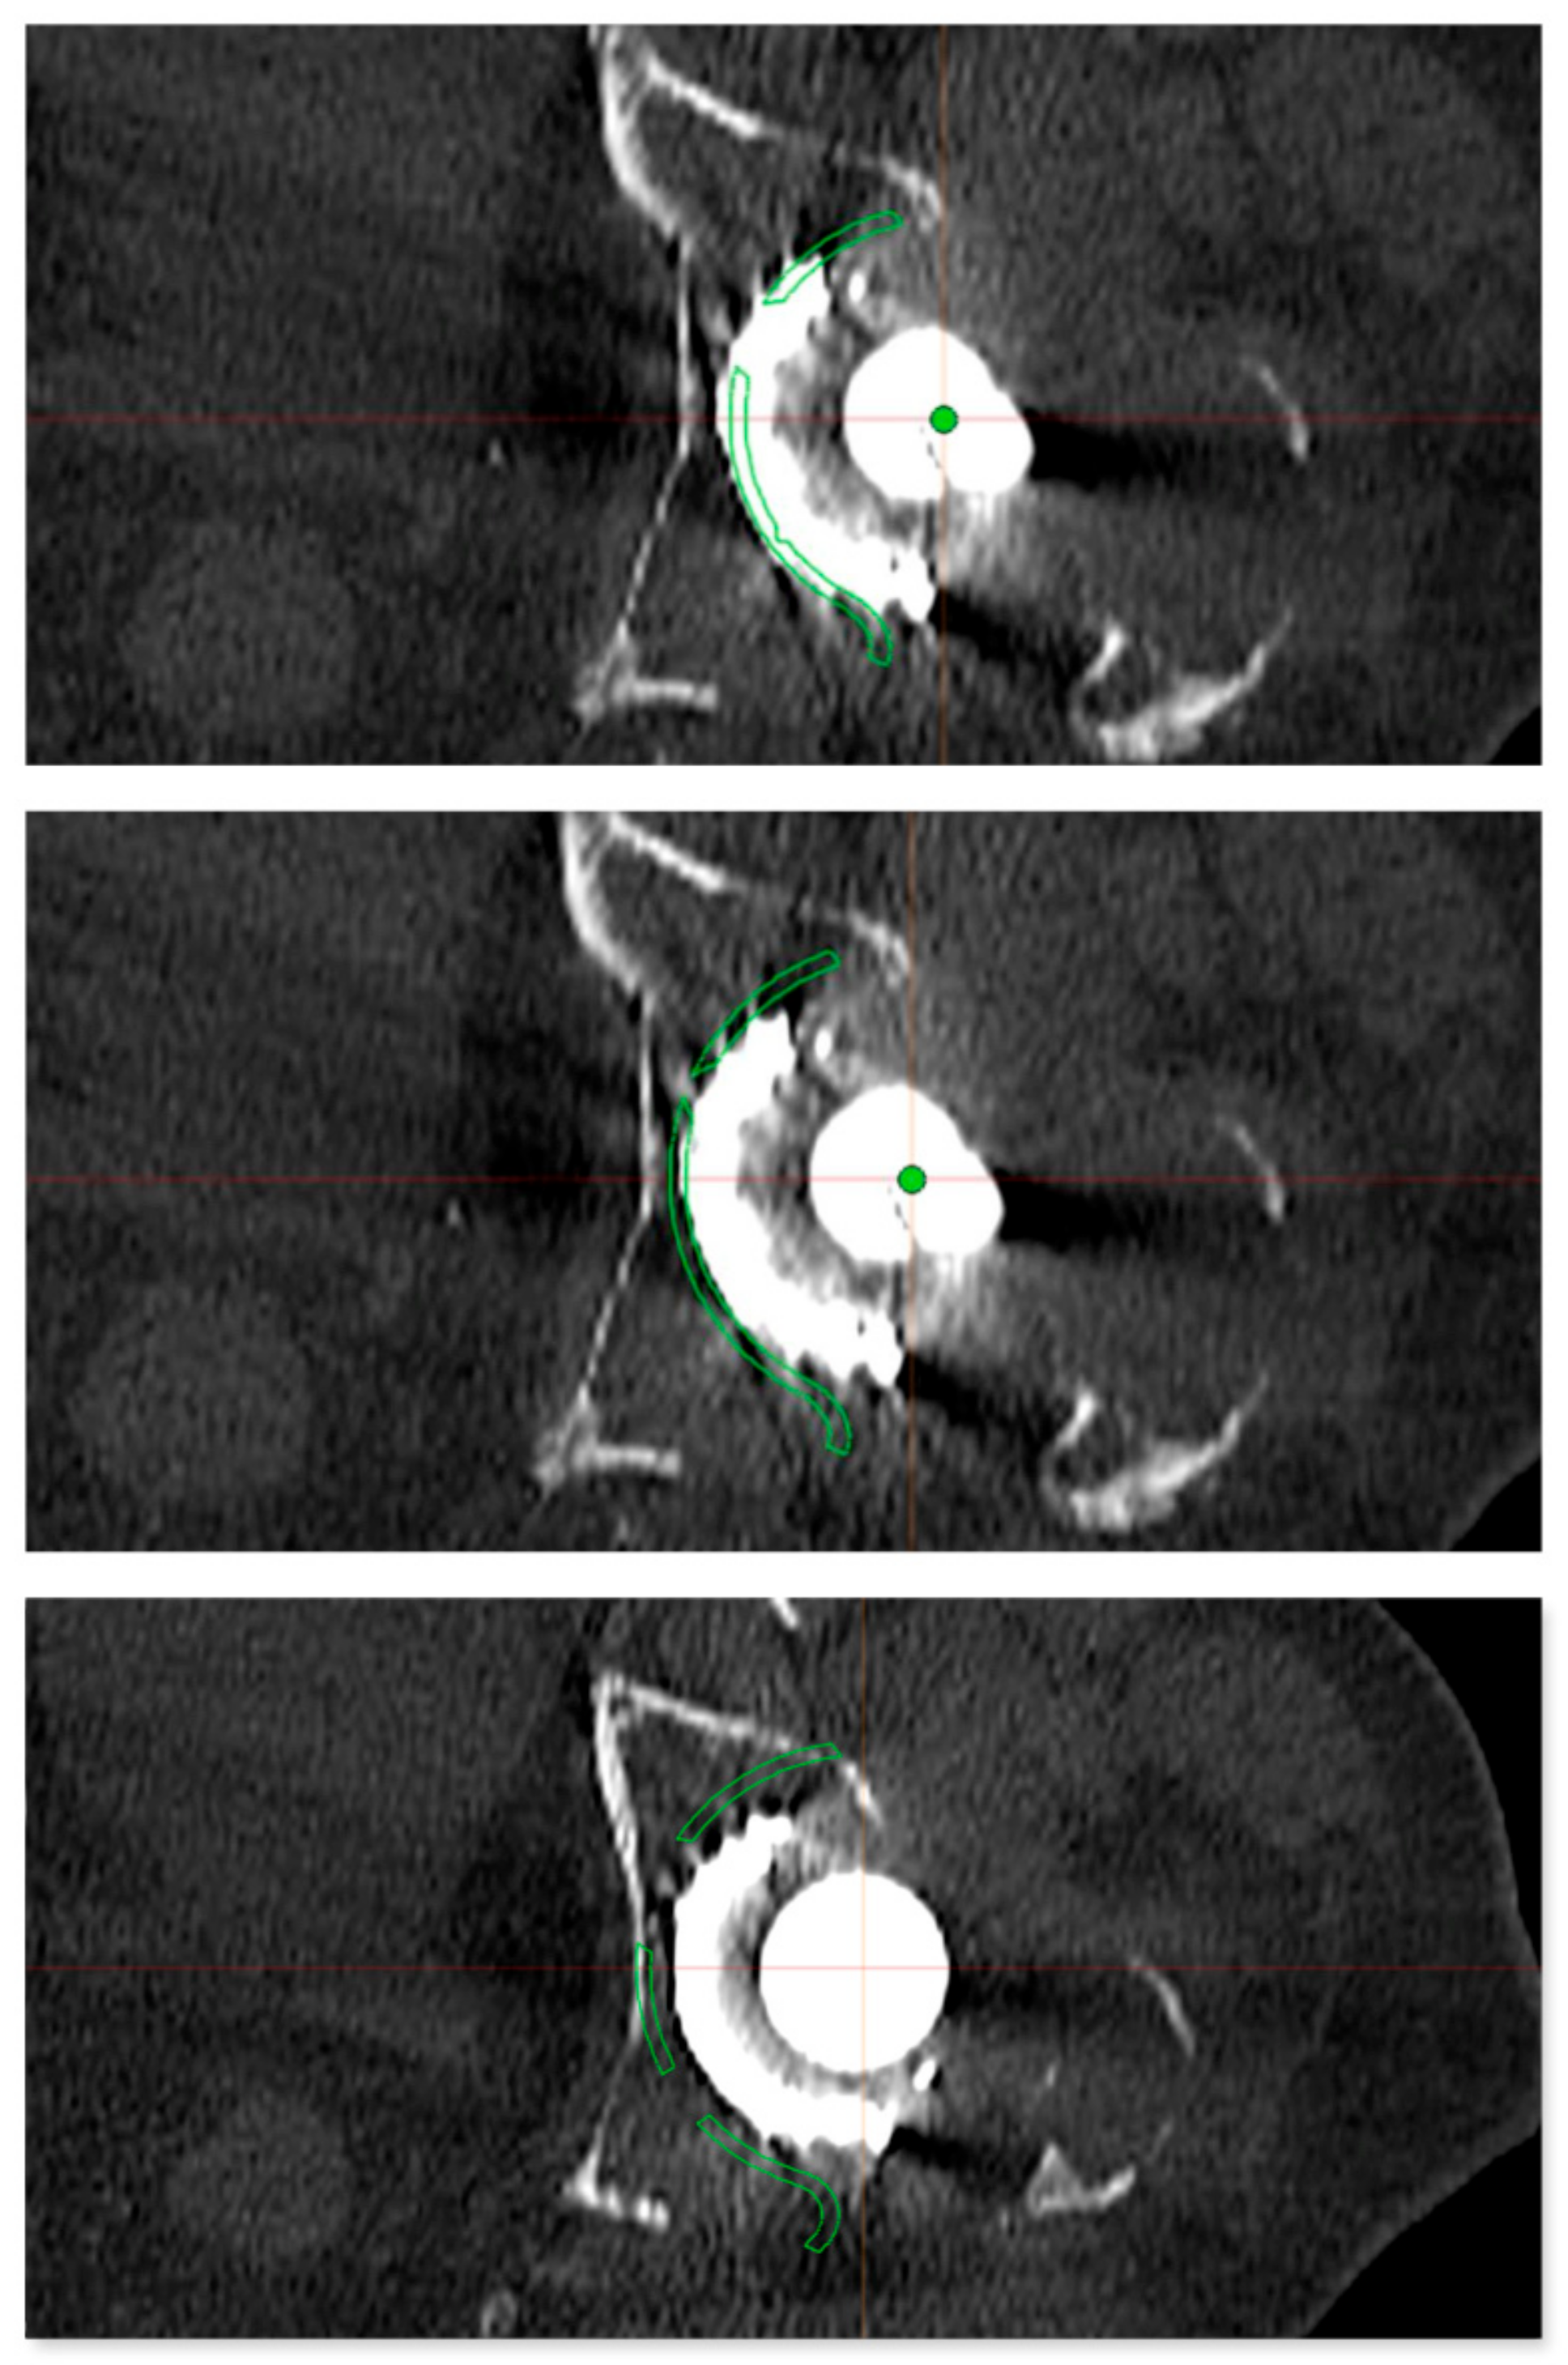

Figure 4. Preoperative planning of the reinforcement cage (Burch Schneider) in the transversal plane of the CT scan. The results of the personalized planning are shown in the center image, indicative of a Burch Schneider reinforcement cage 56 mm in diameter. The upper and lower images show reinforcement cages one size smaller (50 mm; top) and one size larger (62 mm, bottom). In this patient, a 56 mm size reinforcement cage was implanted.